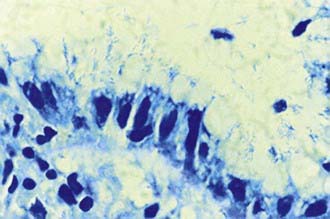

The diagnosis of H. pylori infection is made histologically by demonstrating the organism in the biopsy specimens (Fig. 327-1). Although serologic assays using validated immunoglobulin G (IgG) antibody detection may be helpful for screening children for the presence of H. pylori, they do not help predict active infection or assess the success of antimicrobial eradication therapy. 13C-urea breath tests and stool antigen tests are also noninvasive methods of detecting H. pylori infection. Nonetheless, for children with suspected H. pylori infection, an initial upper endoscopy is recommended to evaluate and confirm H. pylori disease. The range of endoscopic findings in children with H. pylori infection varies from being grossly normal to the presence of nonspecific gastritis with prominent rugal folds, nodularity (Fig. 327-2), or ulcers. Because the antral mucosa appears to be endoscopically normal in a significant number of children with primary H. pylori gastritis, gastric biopsies should always be obtained from the body and antrum of the stomach regardless of the endoscopic appearance. If H. pylori is identified, even in a child with no symptoms, eradication therapy should be offered (Tables 327-2 and 327-3).

image

Figure 327-1 Appearance of Helicobacter pylori on the gastric mucosal surface with Giemsa stain (high-power view).

(From Campbell DI, Thomas JE: Heliobacter pylori infection in paediatric practice, Arch Dis Child Edu Pract Ed 90:ep25–ep30, 2005.)